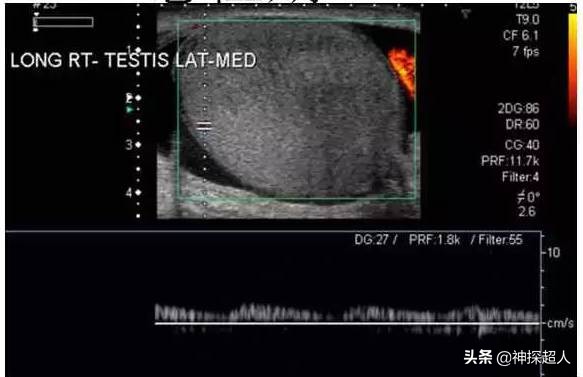

右侧*丸睾**扭转声像图

彩色多普勒超声: 为诊断*丸睾**扭转的首选检查方法,准确率接近90%。超声检查可显示*丸睾**血流信号减弱或消失,还可以帮助区分扭转与附睾炎。*丸睾**扭转者在早期,超声下可见*丸睾**回声轻度肿大,彩色血流信号减少。扭转继续或加重,则*丸睾**明显增大,彩色血流信号明显减少或消失,*丸睾**周围出现少量液性回声,阴囊壁软组织增厚。晚期病例,*丸睾**坏死内部回声不均匀,周围液性回声增多,彩色血流信号消失。

超声检查提示:*丸睾**肿胀近似球形,回声减低,CDFI于*丸睾**内未探及血流信号。